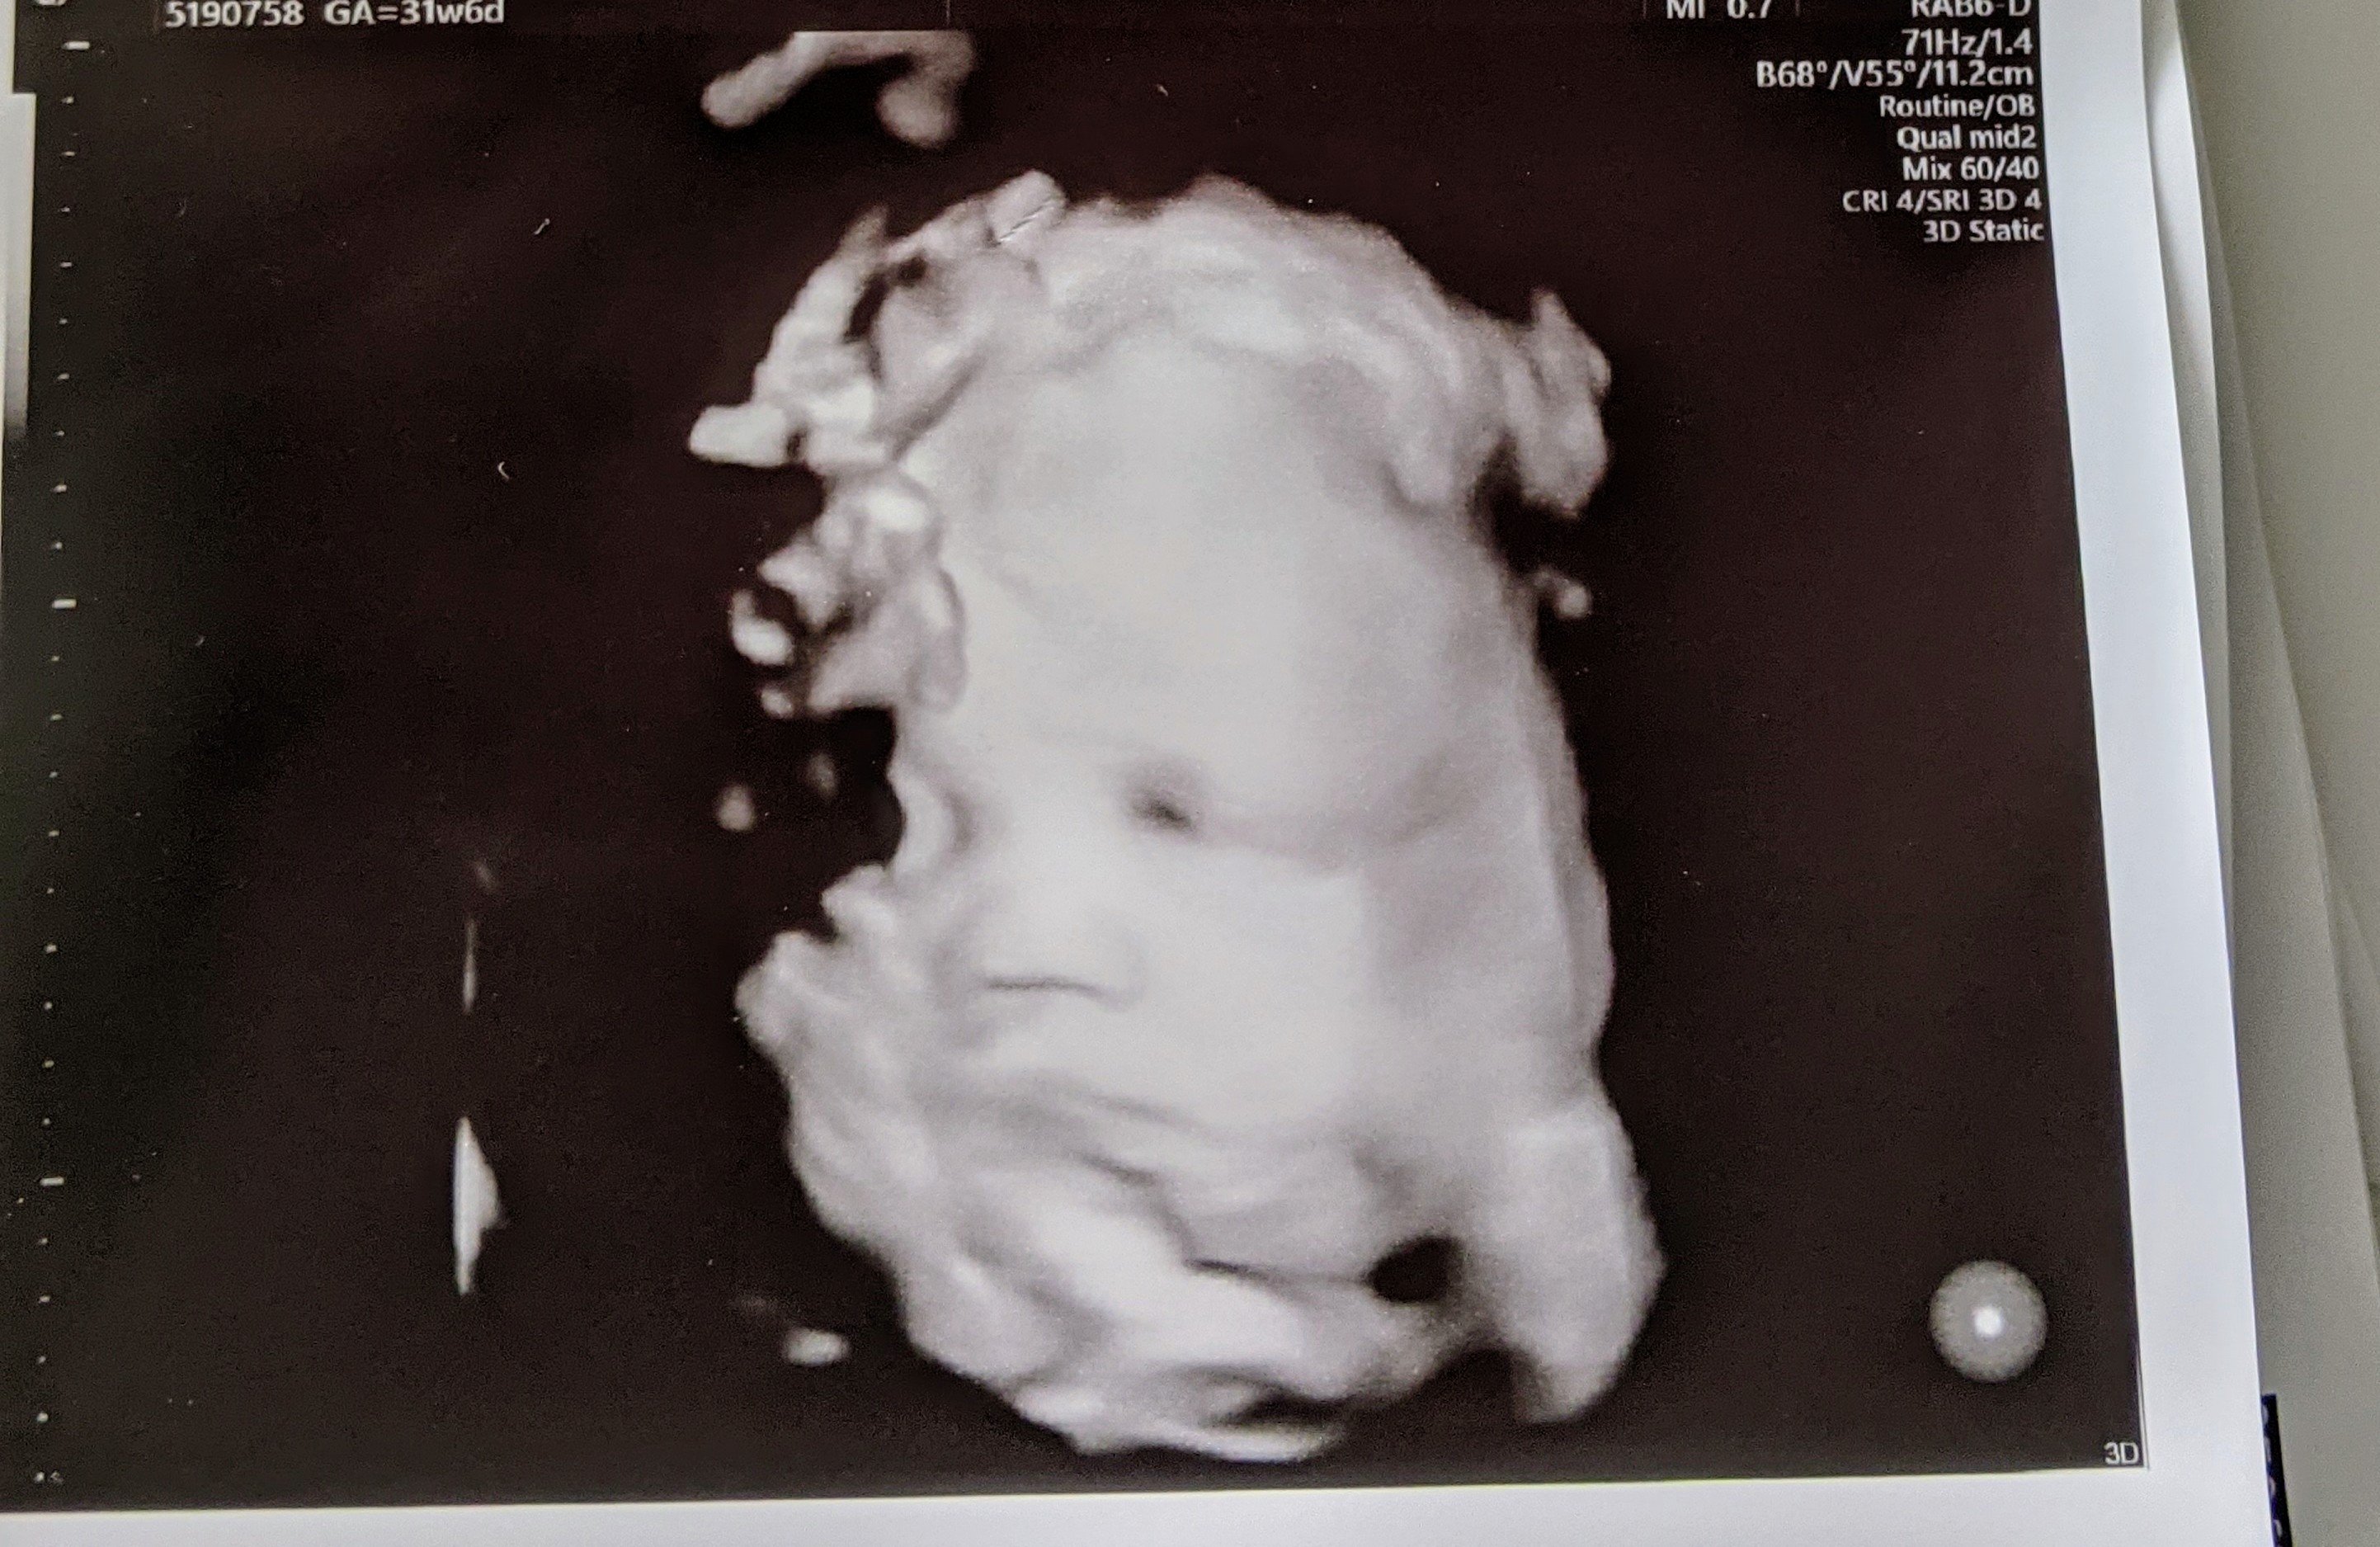

@alexxajams they only tried the 3D for a few minutes, and I think only to try to get a good picture for us. Not sure my regular OB even has a 3D one in their office

Aside from that, baby is looking good.